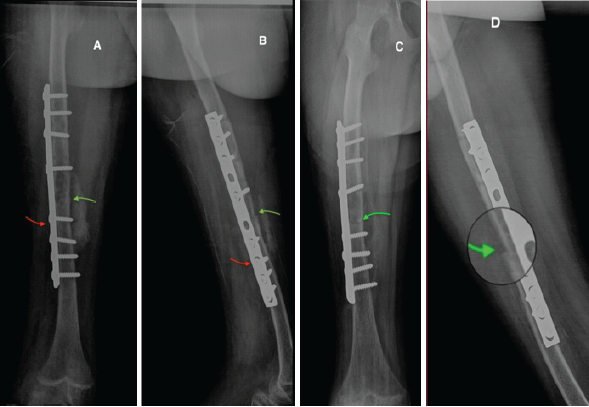

He was discharged on postoperative day 2 with close follow-up scheduled. At 3 weeks, the patient was asymptomatic, with proper wound healing and functional mobility. Radiographs confirmed maintained reduction and early consolidation (Fig. 2). At 6 months, he remained pain-free with good hip mobility and radiological evidence of Grade IV callus formation (Fig. 3).

Figure 2: X-ray follow-up. Immediate post-operative anteroposterior (AP) (A) and lateral (B) radiographs showing fracture line reduction (green arrow) and placement of osteosynthesis material (red arrow); (C) AP; and (D) lateral radiographs at 3 weeks postoperatively showing maintained reduction and Grade II consolidation (green arrow).